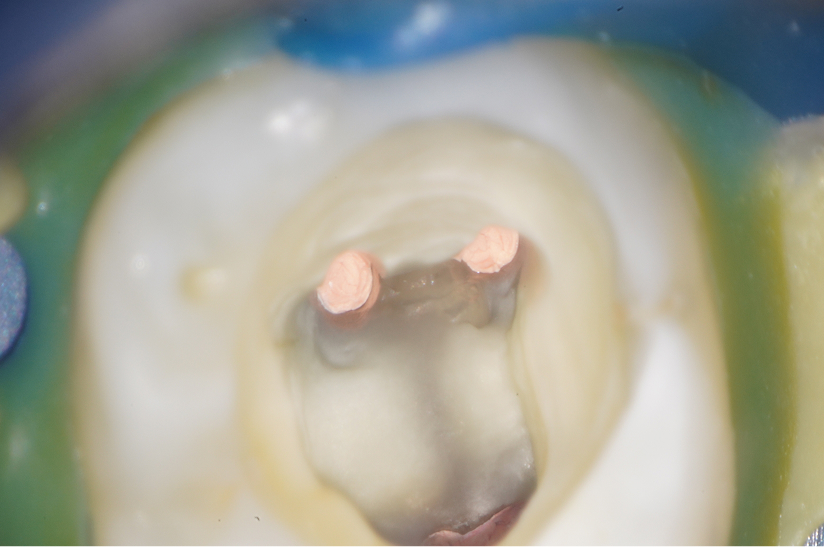

大臼歯の再根管治療を行った症例

タップで写真の拡大ができます。

Before&After(根管治療)

Before

Before&After(根管充填)

主訴

歯茎が腫れて、噛むと違和感がある

治療内容

再根管治療(大臼歯)

治療期間

1ヶ月

治療費用

165,000

治療の

リスク

処置中に歯肉縁下におよぶ重度のう蝕や破折を認めた場合、治療を中断する可能性があります。術後も症状が残る場合は追加の処置が必要になる可能性があります。